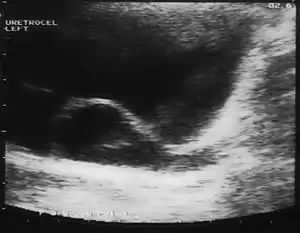

Since the advent of the ultrasound, most ureteroceles are diagnosed prenatally. The pediatric and adult conditions are often found incidentally, i.e. through diagnostic imaging performed for unrelated reasons.

IVU-shows Adder head appearance or Cobra head appearance. Cystoscopy-shows translucent cyst which is thin walled surrounding ureteric orifice